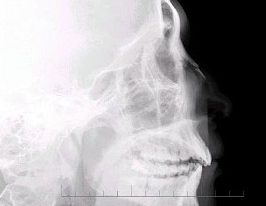

40、多项选择题

男,24岁,鼻部被击伤,如图所示,最可能的诊断是()

A.鼻骨中段见透亮线影

B.鼻骨远端稍塌陷

C.鼻骨骨折处可见小骨片影向下方分离

D.考虑为鼻骨线性骨折

E.鼻骨粉碎性骨折